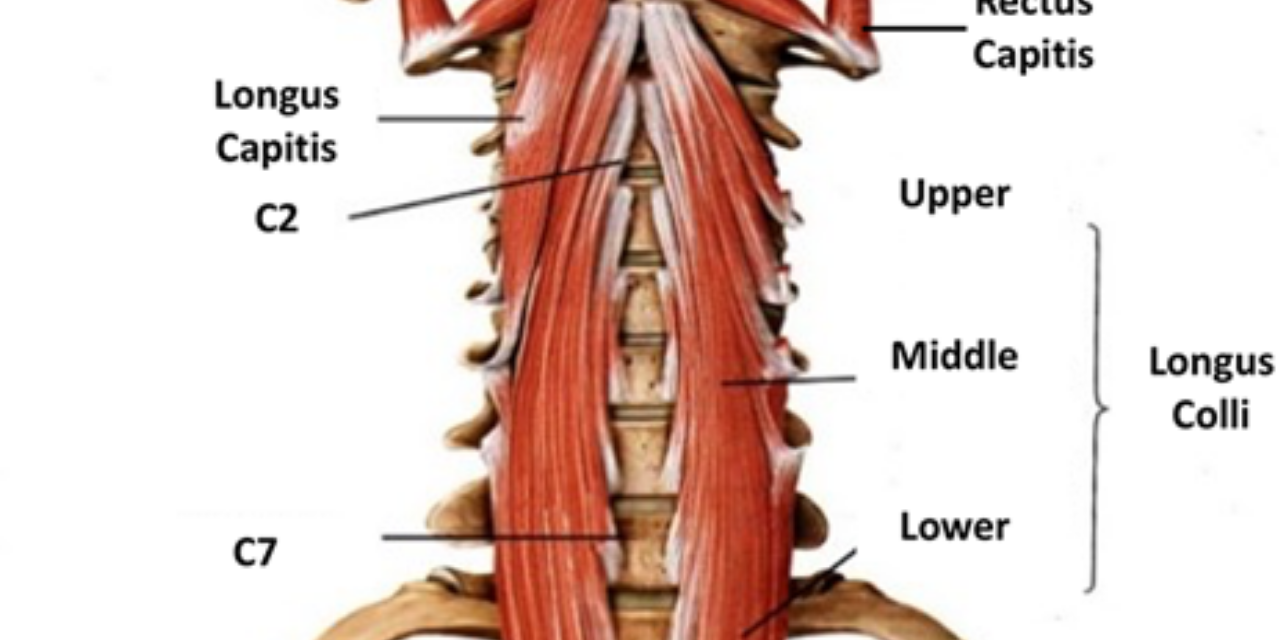

The deep neck flexors include four muscles that lie behind the trachea on the front of the cervical spine. The group includes the longus colli, longus capitis, rectus capitis, and longus cervicis. Due to their proximity to the spine and their short length, the muscles are primary stabilizers of the cervical spine.

“Current results confirmed the presence of cervical multifidus and longus colli muscle atrophy in subjects with chronic radicular neck pain.” (1)